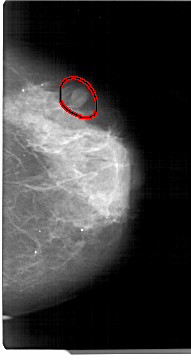

A_1305_1.RIGHT_CC

RIGHT_CC LINES 5386 PIXELS_PER_LINE 2851 BITS_PER_PIXEL 12 RESOLUTION 43.5 OVERLAY

FILE: A_1305_1.RIGHT_CC.OVERLAY

TOTAL_ABNORMALITIES 1

ABNORMALITY 1

LESION_TYPE MASS SHAPE OVAL MARGINS CIRCUMSCRIBED

ASSESSMENT 4

SUBTLETY 4

PATHOLOGY BENIGN

TOTAL_OUTLINES 1

BOUNDARY